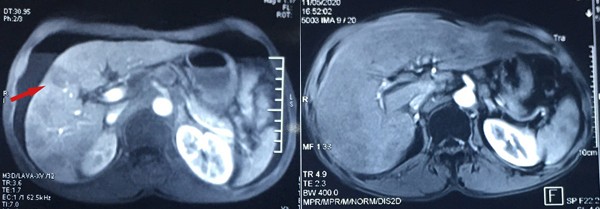

BS Nguyễn Trọng Hiếu, Trưởng khoa Nội 2 cho biết, khi vào viện, bệnh nhân có khối u 1/3 dưới thực quản khá to, kích thước 5x2,5 cm, có nhiều hạch xung quanh, hạch lớn nhất hơn 2 cm.

Đặc biệt, ung thư đã di căn xuống gan với ổ lớn nhất đường kính 3 cm. Bác sĩ chẩn đoán bệnh nhân đã mắc ung thư giai đoạn muộn, các biện pháp phẫu thuật, điều trị tại chỗ không còn tác dụng nên chỉ định điều trị hoá chất toàn thân.